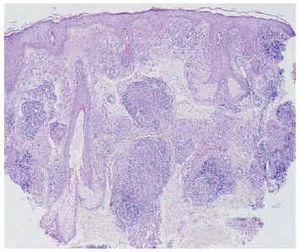

Fig. 3.--Imagen a pequeño aumento que muestra la presencia de numerosos agregados focales de histiocitos, muchos de ellos de gran tamaño, rodeados de una corona linfocitaria, dispuestos mayoritariamente a lo largo de la dermis papilar y reticular alta. (Hematoxilina-eosina, ×40.)